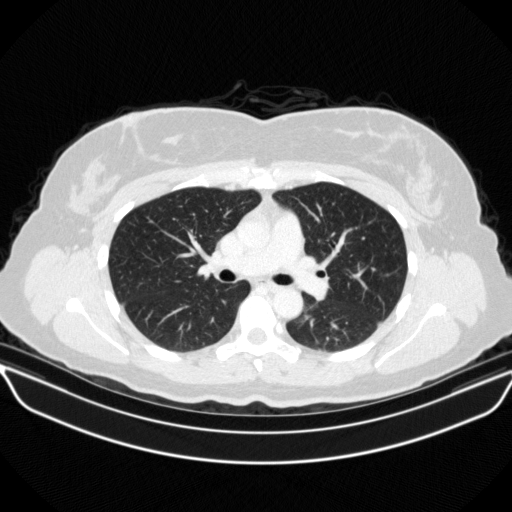

Original VENOUS CT scan

Full window (WL 1023.5, WW 4095 β†’ Low βˆ’1024, High +3071)

Lung window (WL -600, WW 1500 β†’ Low βˆ’1350, High +150)

Mediastinum window (WL 40, WW 400 β†’ Low βˆ’160, High +240)